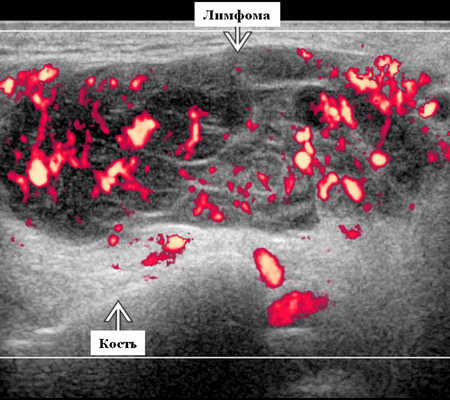

Цветной допплер. Узловая НХЛ. Выраженная центральная или внутриузловая гиперваскуляризация. Паренхима при неходжкинской лимфоме более диффузная железистая гиперваскуляризация. Васкуляризация от умеренной до выраженной в плохо очерченных образованиях.